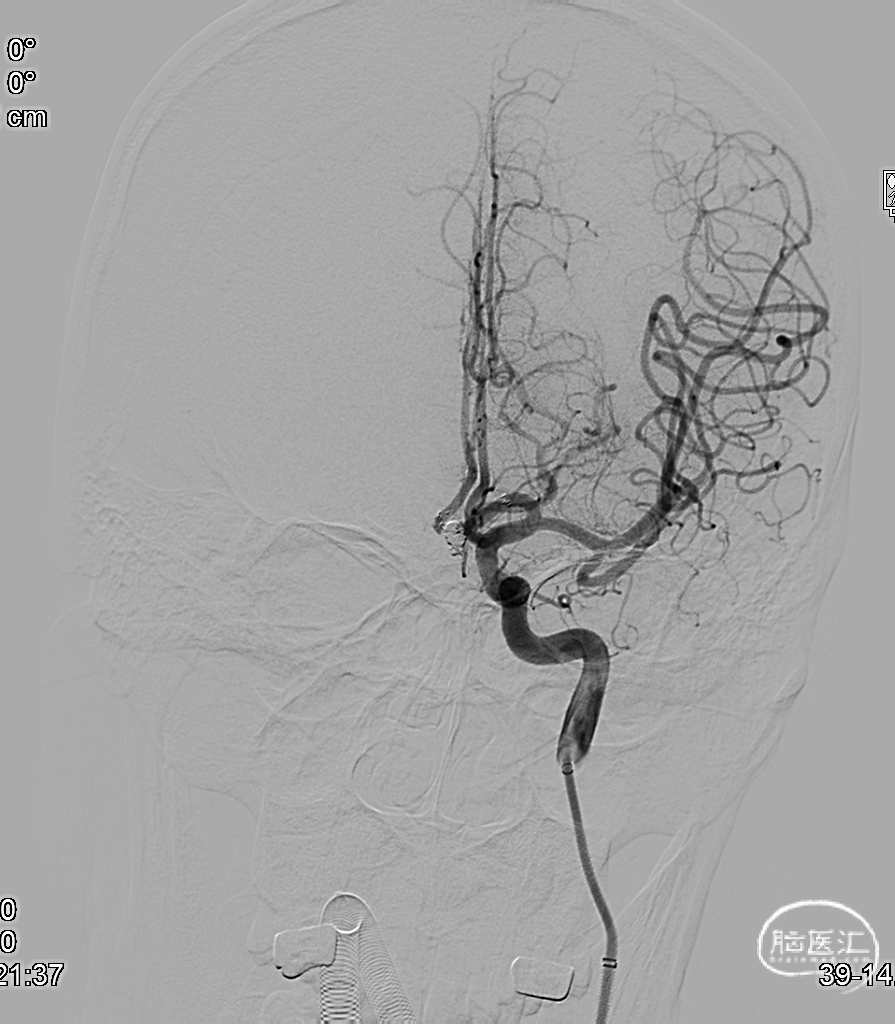

术后正侧位造影。